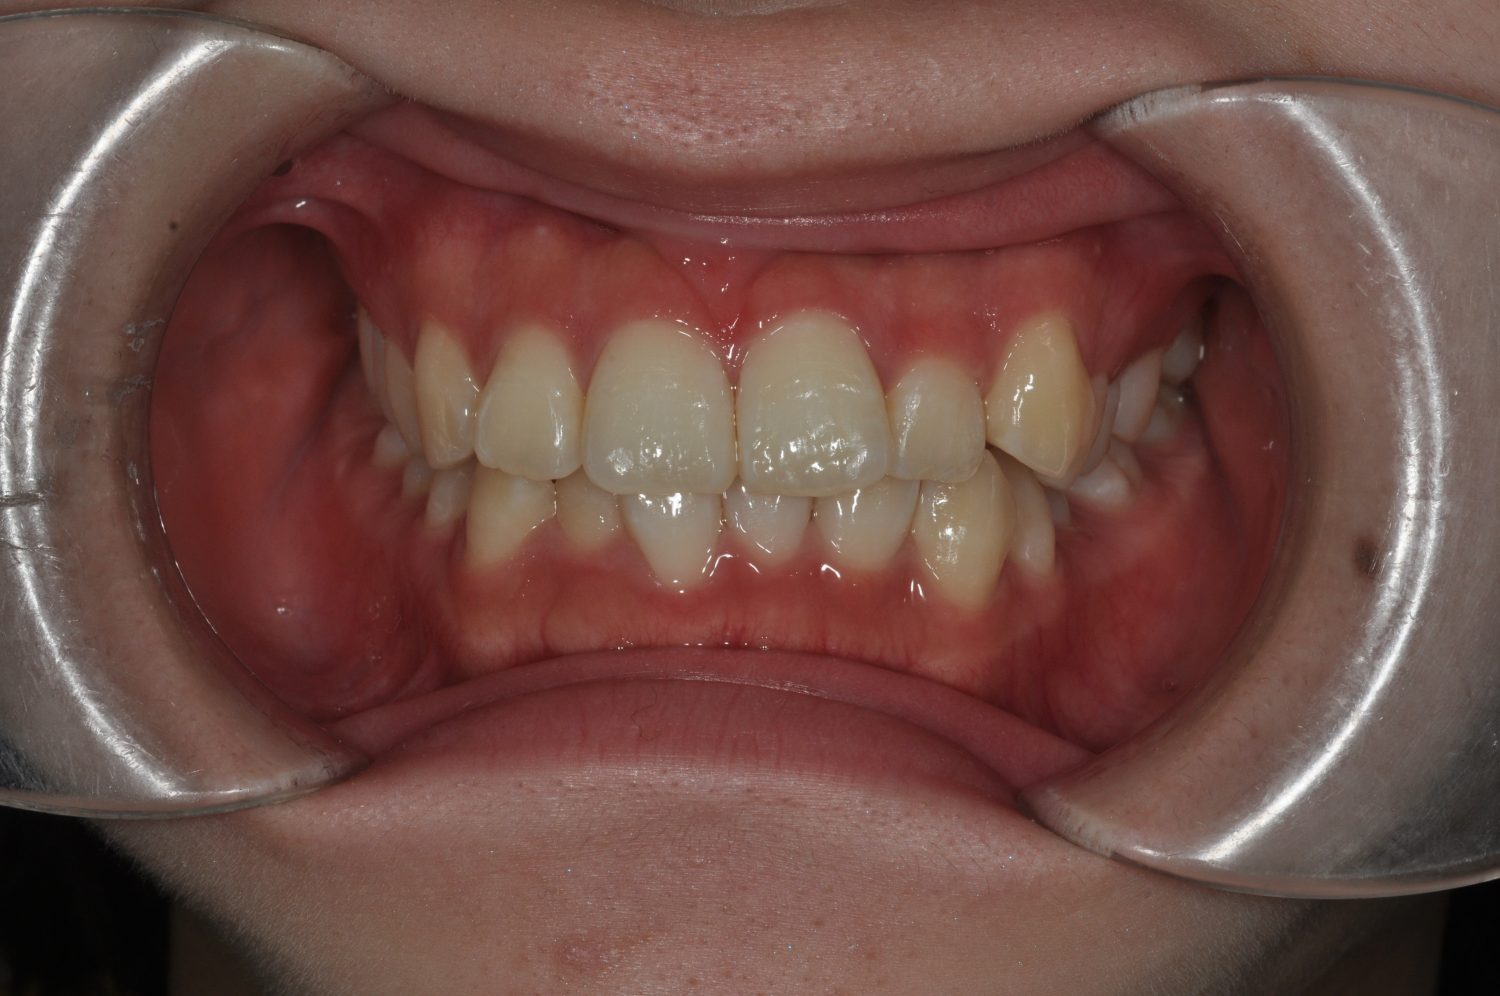

| 主訴 | 口上下顎のガチャガチャが気になる |

| 治療内容 | 歯冠幅径が大きいことから、IPRを併用した非抜歯治療 |

| 治療費 | Ⅱ期治療費:247,500円(税込) 調整料 5500円(税込)×11回 保定時:22,000円(税込) 計 330,000円(税込) |

| 治療期間 | 1年2ヶ月 |

| 治療回数 | 13回 |

| 想定されたリスク | 矯正中の清掃状況によってはむし歯や歯周病のリスクがありました。歯根吸収や歯肉退縮のリスクもありました。 |

Ⅰ期治療で前歯部反対咬合をセクショナルアーチとMPAを使用して改善した後、成長観察を行っていました。永久歯が萌出したため、Ⅱ期治療を開始することとなった。上下顎とも骨格的に問題がなかったため、非抜歯で治療を行った。